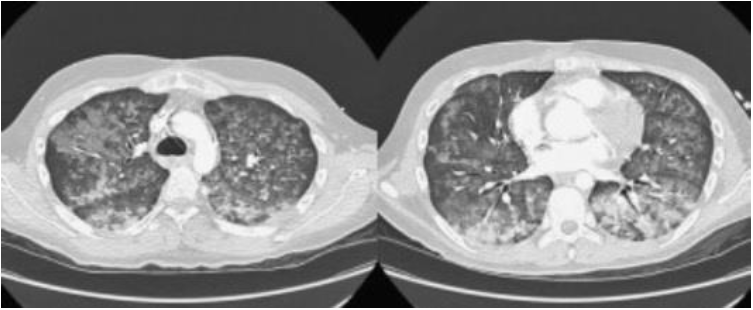

As imagens radiológicas a seguir apontam um diagnóstico de: